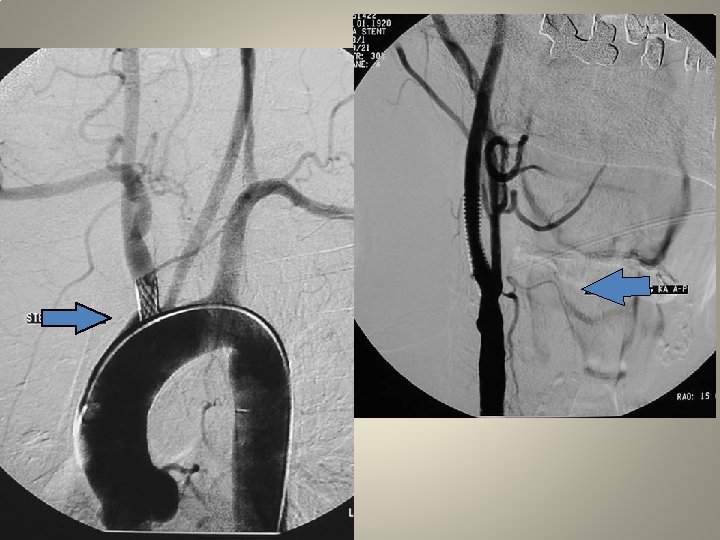

Neden stent? TANDEM lezyon

Neden stent? Distal emboli koruma

Neden stent? Eş zmanlı komplikasyon idaresi

Vasküler erişim • Kateterizasyon: uzun re-inforced sheats (terumo, arrow, cook) uzun diagnostik kateter 120/125 cm Hidrofilik (Terumo 0. 035 -38 stiff or roadrunner-Cook) teller Hidrofilik olmayan (amplatz) teller

Uzun kılıf • Standard kılavuz kateterlere oranla artmış stabilite • Geniş lümen • Bükülmeye direnç • Hidorfilik kayganlık, ilerletilebilme

Uzun kılıf • Terumo Destination 6 F, 90 cm, iç lümen • Cook Shuttle, 5 F 90 -110 cm, 0. 074 inch 6 F 80 -110 cm, 0. 087 inch • Arrow…….

Koruma şemsiyesi • Spider (ev 3) • Filter. Wire (boston) • Angioguard (cordis)

stent • • Açık yarı-açık kapalı hücreli Çok katmanlı